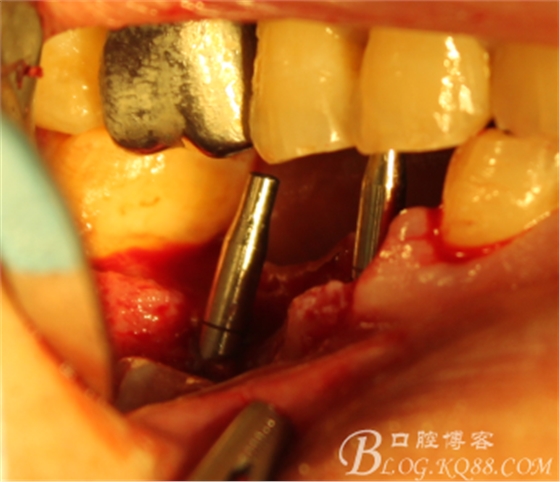

手術(shù)全程

翻瓣,拔除C5,跟尖端有吸收

徹底搔刮肉芽,定點(diǎn),正對(duì)顎尖,擴(kuò)孔同期行慢轉(zhuǎn)收集自體骨

植入植體

C6頰側(cè)填入自體骨,嚴(yán)密縫合關(guān)閉創(chuàng)口

三維檢查種植體位置,方向,平行度